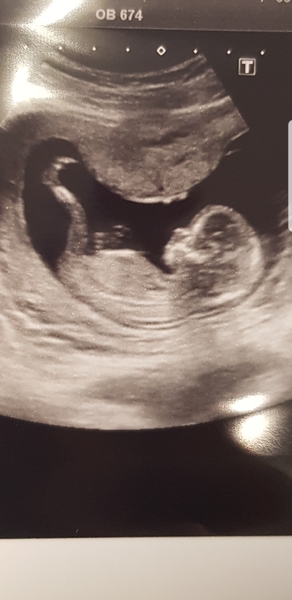

Ahhhh @QforCucumber thats a class photo. Look at the length of the legs. Enjoy the buzz.

@QforCucumber ah congratulations so glad your scan went well, that's a brilliant photo as well!! My baby wouldn't stay still long enough so photos weren't to clear x

Had my scan yesterday and thankfully all seemed normal. The tech labeled the twins "Baby A" and "Baby B" and apparently they will be easy to tell apart from now on because the one currently closer to the cervix, A, will always be there. Those two tiny hearts are going around 155 bpm. Seeing the umbilical cords and the blood flow was really amazing. And they were moving around! I can't believe how active they were and of course I can't feel a thing yet! I'm just minding my business and they're kicking and doing flips. The babies actually look human-ish now, not just the blobs I saw in early weeks when the endocrinologist was making sure they'd implanted properly.